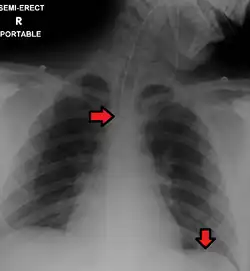

Confirming placement

It is necessary to confirm placement of the endotracheal tube to ensure that the tube is properly positioned within the trachea and has not accidentally passed into the esophagus instead. Additionally, it is important to confirm that the endotracheal tube was not placed too deep in the trachea where is may only be ventilating one of the lungs due to it being positioned within a mainstem bronchi (frequently the right mainstem bronchi due to a more obtuse angle than the left). The gold standard for confirming successful placement of an endotracheal tube is direct visualization of the tube passing through the vocal cords and positive end-tidal carbon dioxide on capnography. Secondary methods of confirmation include oxygen saturation, chest x-ray, ultrasound, condensation in the endotracheal tube, equal chest rise, breath sounds heard on both sides of the chest (often with the assistance of a large tidal volume breath), and an absence of breath sounds over the epigastrium. No single method of confirming placement is 100% reliable so multiple methods of confirmation should be utilized.[6][17][18]